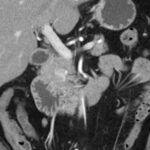

Paciente femenina de 48 años de edad que ingresa a Hospital Sanatorio Franchin por síntomas de cefalea y mareos, cuadro que se hace progresivo, presentando síncopes y posteriormente alteración del estado de conciencia. Los exámenes clínicos revelan una glucosa de 40 mg/dl, concomitante con insulina alta y péptido C elevado. Ingresa de forma programada para realización de duodeno pancreatectomía el 29 de mayo de 2021. Imágenes diagnósticas muestran estudio trifásico de tomografía de abdomen, lesión nodular en la cabeza del páncreas con ávido realce en fase arterial que en resonancia magnética se observa hiperintensa en T2, presenta restricción con la difusión y caída de la señal en el ADC. Además presenta realce tras la administración de contraste con gadolinio.

Mujer de 36 años que ingresa a Hospital Sanatorio Franchin el 11 de octubre de 2023 de forma programada para realización de duodeno pancreatectomía cefálica por tumor de cabeza de páncreas en estudio. Refiere hallazgo de lesión en forma incidental durante estudio de control hace dos meses por presentar antecedentes familiares (neoplasia endocrina múltiple). Se interna para manejo quirúrgico. Estudios de tomografía revelan formación nodular localizada en cabeza y cuerpo pancreático de paredes gruesas que mide 24 x 28 mm, que en resonancia se muestra hiperintensa en T2 y realce periférico luego de la administración de contraste endovenoso. Presenta restricción en la difusión con caída de la señal ADC, por lo que se vincula con una lesión de alta celularidad.

Ahora bien, como se mencionaba al principio, el estudio ecográfico es de muy baja sensibilidad y se identifique o no la lesión por este estudio, nuestro siguiente paso en el algoritmo diagnóstico de esta lesión es la tomografía. Esta es la prueba no invasiva inicial, con una sensibilidad del 63% al 83%, y detecta del 70% al 80% de los tumores. Esta debe realizarse como un estudio trifásico: fase arterial temprana a los 30 segundos, fase venosa a los 70 segundos, fase tardía de 3 a 5 minutos. La característica de estos tumores por tomografía es que se presentan como una masa sólida que tiene un ávido realce en la fase arterial, cuyo realce se mantiene y se observa más tenue en la fase venosa y en los tiempos tardíos la lesión se homogeniza.

Para mi caso, y dando una visión general de los métodos de imagen no invasivos en esta revisión retrospectiva, solo a uno de los pacientes se le detectó la lesión por ecografía, donde se visualizó una lesión nodular hipoecogénica en el cuerpo del páncreas. A los demás pacientes se les detectó la lesión por tomografía en estudio trifásico, donde resaltan las características ya descritas por la literatura de lesiones hipervasculares con intenso realce en fase arterial, localizadas en diferentes partes del páncreas, como cabeza, cuerpo y cola.

La resonancia magnética confirmó aún más el diagnóstico de las lesiones ya previamente visualizadas en tomografía en esta revisión, con realce de las lesiones en secuencias T1 y contraste con gadolinio, y en las secuencias funcionales con restricción de la lesión y caída de la señal en el mapa de ADC.